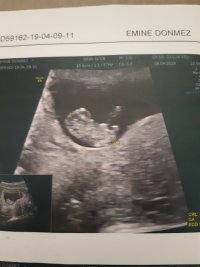

@Zerre tam çekememişsin şu apış arasındaki çıkıntıyı çekip atsana bana göre kız mrk ettim bi daha sadece o bölümü çekip atabilir misin kız harici bişi çıksın saçlarımı yolarım

Benm kendi doktorum olmadğı içn 12. hftada farklı bir doktora ikili test yaptrmştm ve cinsiyetinin kız olduğunu söylemşti

ama 16. haftada tekrar gittiğimde kendi doktorum erkek olduğunu söyledi sizce nedir? doğru sonuç için detaylıyı mı beklemeliyim???

Belittiğiniz haftalarda cinsiyet tahmininde yanılmalar olabilir. Gebeliğin 17-18-20 . haftalarında bebeğinizin cinsiyetini net olarak öğrenebilirsiniz.